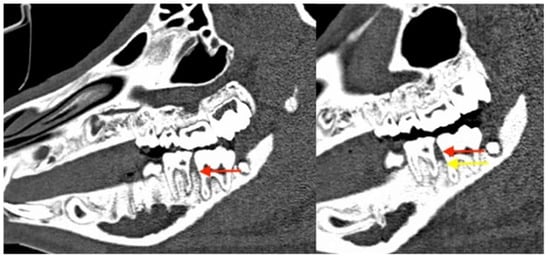

3.2.1. Clinical Evaluation

3.2.3. Radiological Evaluation